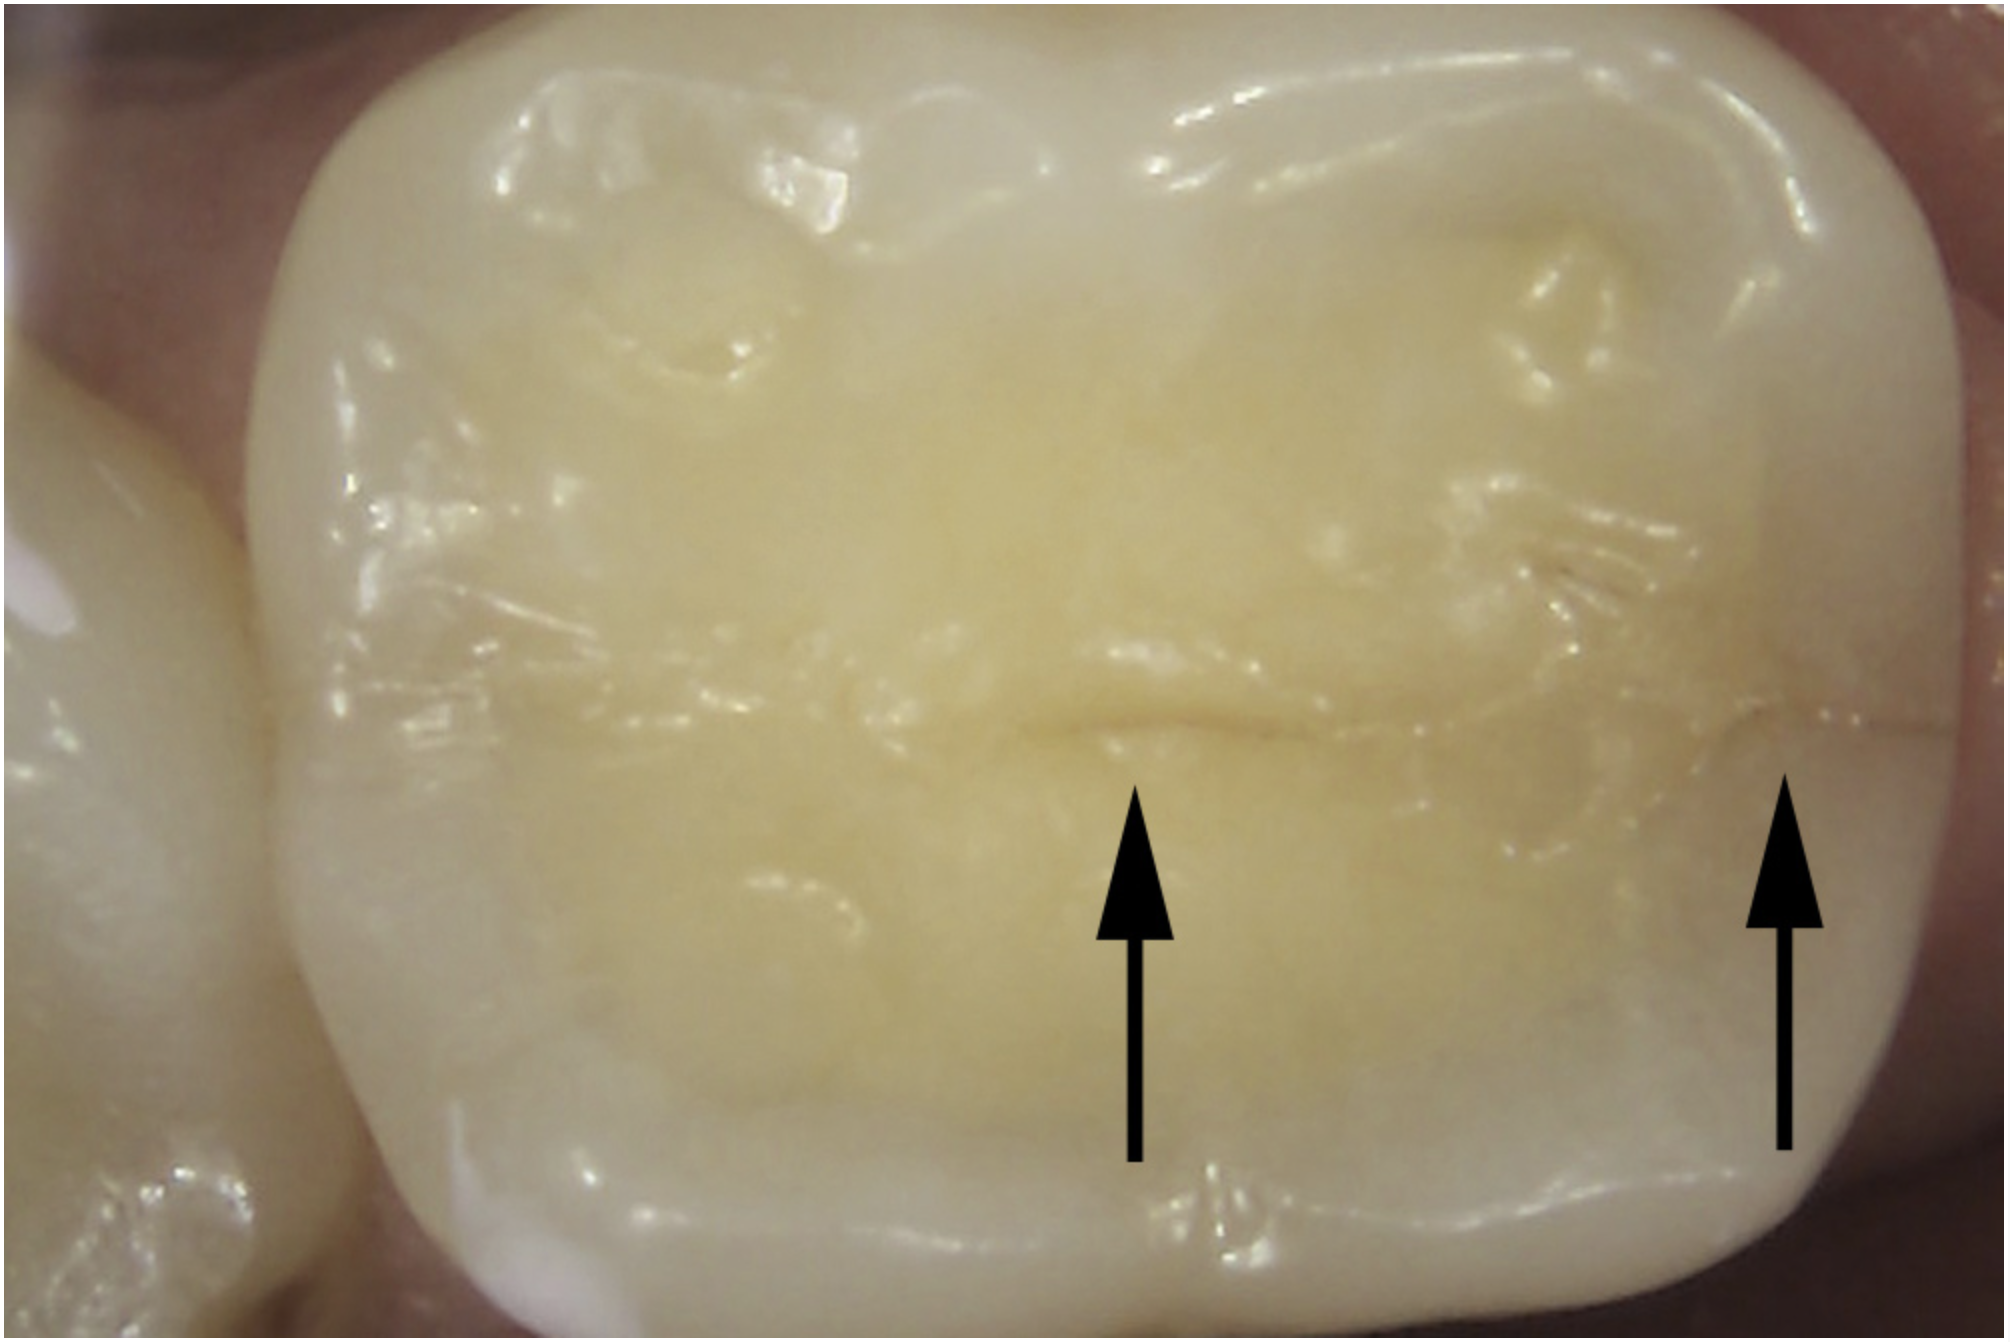

Pathologic Consequences

The detrimental effects of vertical cracks on the dentition and surrounding tissues stem mostly from bacterial invasion into the microscopic space of the crack, as well as physical irritation and liquid microleakage, even though the separation of the segments may not be clinically visible.3,5-7 As bacteria penetrate cracks, they invade underlying structures, such as the coronal dentin, pulp, root structure, and periodontal tissues, leading to varying degrees of pathologies. Enamel cracks have been found to provide caries-producing bacteria access to the dentin-enamel junction, leading to caries inside the tooth without any externally visible evidence (Figure 1).5 Dentin cracks are pathways of bacteria to the dentinal tubules and pulp, leading to various pulpal pathologies, including reversible and irreversible pulpitis and pulp necrosis.6,8

Fig 1. Decalcification in enamel along a crack line (arrow) and caries at the dentin-enamel junction of a mandibular left first molar (disto-occlusal view).

Figure 1